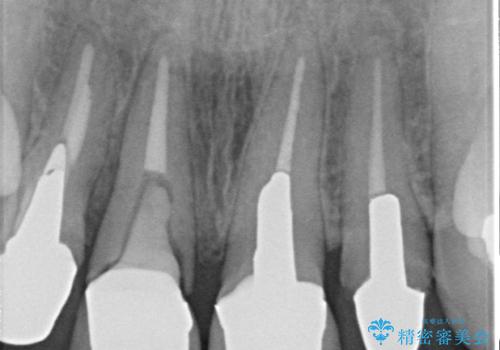

- 右上の前歯が折れてしまったので診て欲しいといらっしゃった方の症例です。

右上1番目の歯は保存不可能だったため抜歯し、ブリッジによる補綴を行いました。

- 根管治療により痛みや腫れがひかない事や、術後に痛みや腫れが生じる事、治療によるファイル破折やパーフォレーションなどの偶発症、術後の歯根破折を生じる可能性もあります